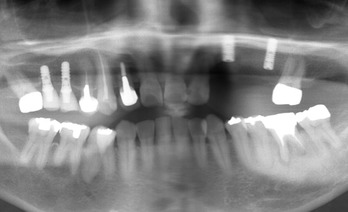

抜歯前の状態が以下のレントゲンです。

抜歯後、インプラント埋入手術を行ったのが以下のレントゲンです。

中心(前歯)に近いインプラントは、

ストローマンの新しいタイプである ボーンレベル インプラント です。

奥の1本だけは、従来からあるスタンダードプラス インプラント(SLA) です。

骨吸収も大きく難しい治療でした。